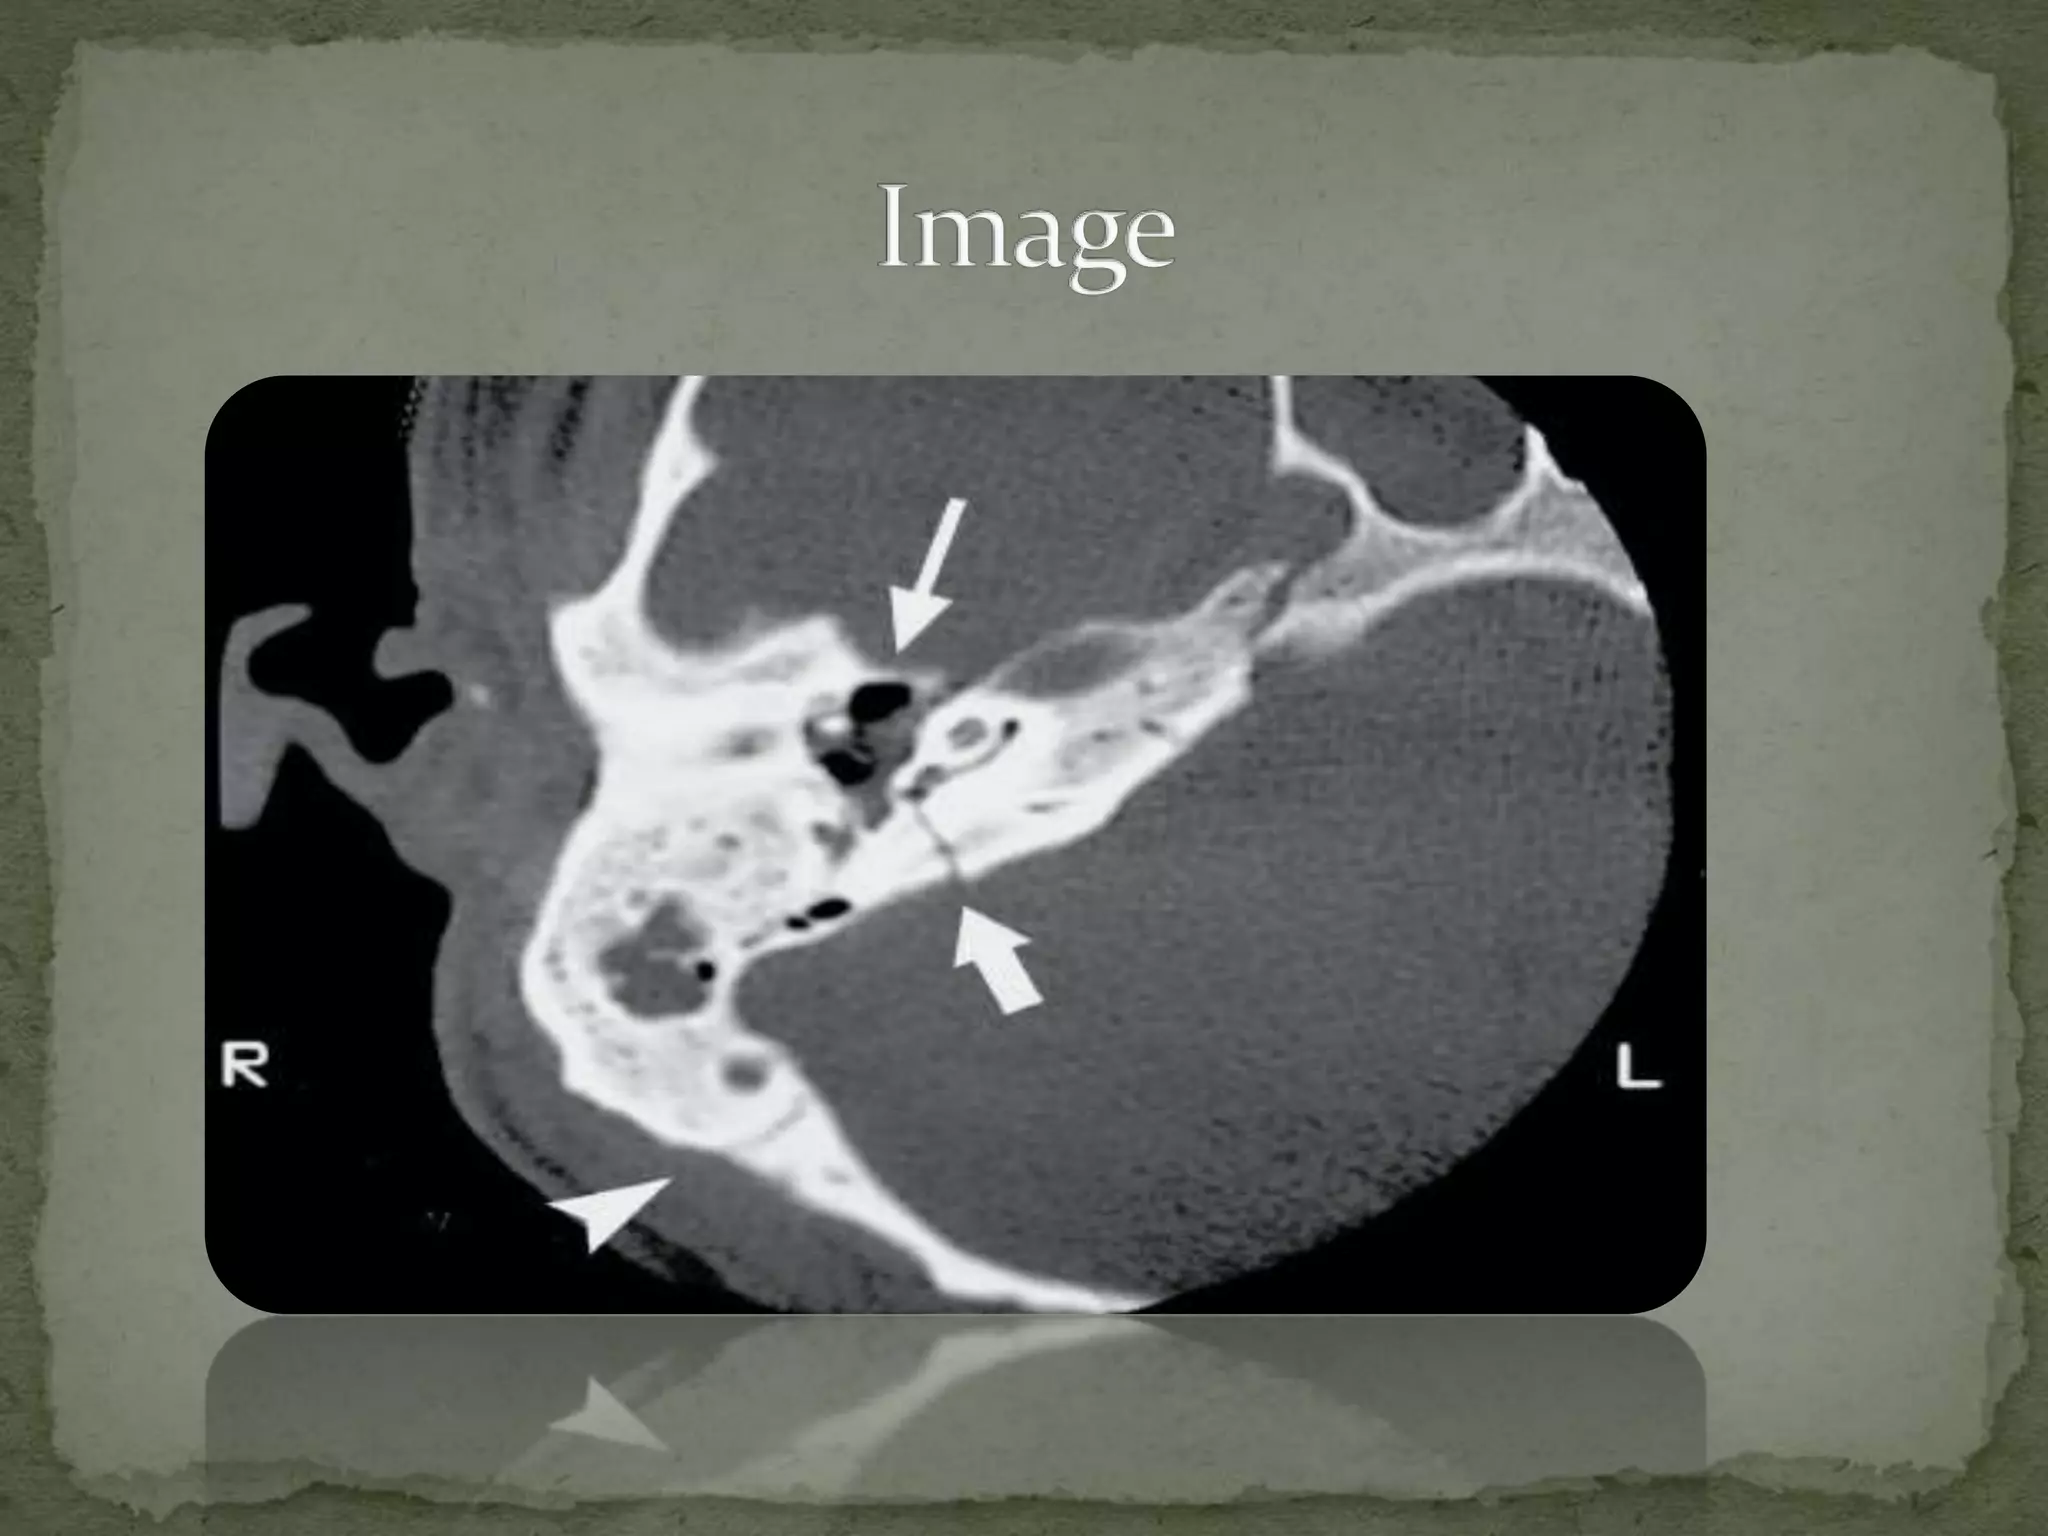

Basilar Skull Fracture Ppt . They can be diagnosed through ct scans or by clinical signs such as bloody discharge from the ear, raccoon eyes, or. Basilar skull fractures occur when there is a break in the base of the skull. Basilar skull fractures are commonly. Clinical signs of basal skull fractures include raccoon. Basal fracture • a basal fracture occurs in the floor of the skull: The areas around the eyes, ears, nose, or back, near the spine. Basal skull fractures occur in the base of the skull and involve fractures of the temporal, occipital, sphenoid, or ethmoid bones. Examination revealed right facial motor weakness, tenderness over the right mastoid bone, and right hemotympanum. Ct scan showed a transverse temporal bone. In addition to the above types, fractures can also.

Transverse transsphenoidal basilar skull fractures with carotid Basilar Skull Fracture Ppt Ct scan showed a transverse temporal bone. Basal fracture • a basal fracture occurs in the floor of the skull: They can be diagnosed through ct scans or by clinical signs such as bloody discharge from the ear, raccoon eyes, or. Examination revealed right facial motor weakness, tenderness over the right mastoid bone, and right hemotympanum. Basilar skull fractures occur. Basilar Skull Fracture Ppt.